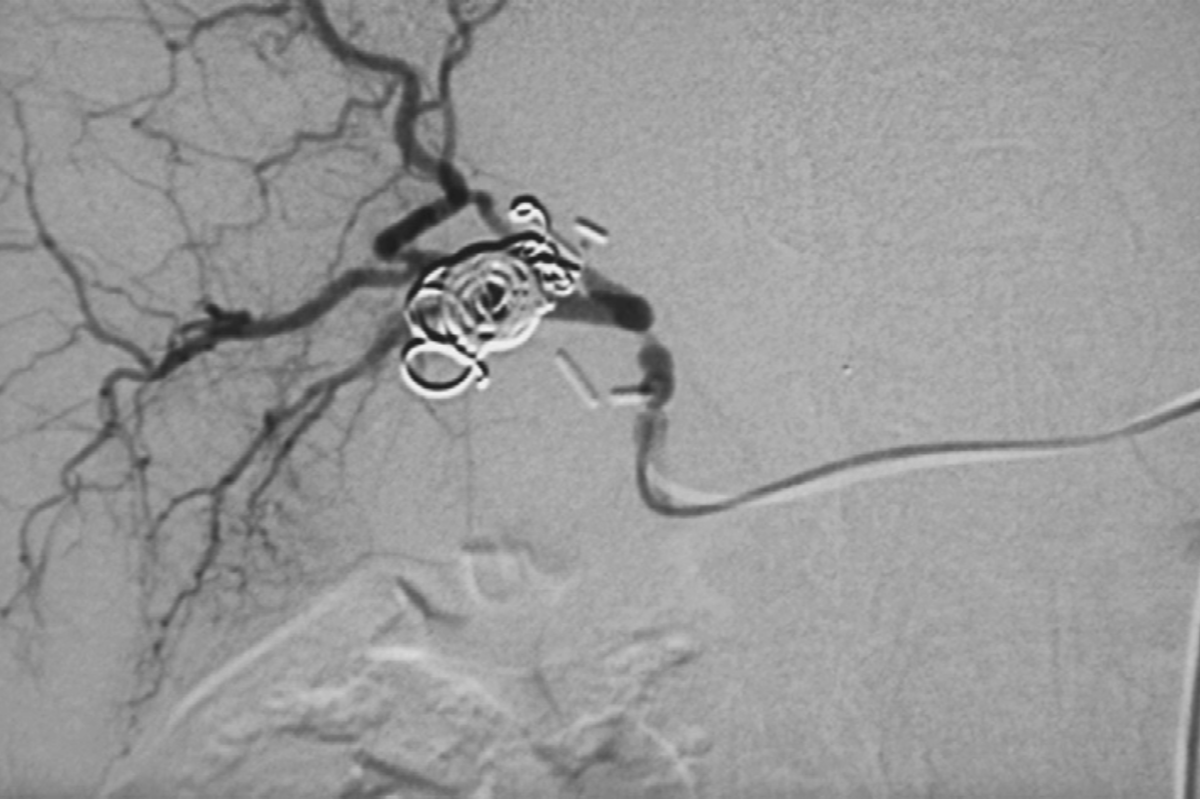

Interventional Radiology (IR) uses real-time imaging such as X-ray, ultrasound, CT, or MRI to guide tiny instruments through the body for treatment — without large surgical incisions.

Case's Video Gallery

Video Gallery